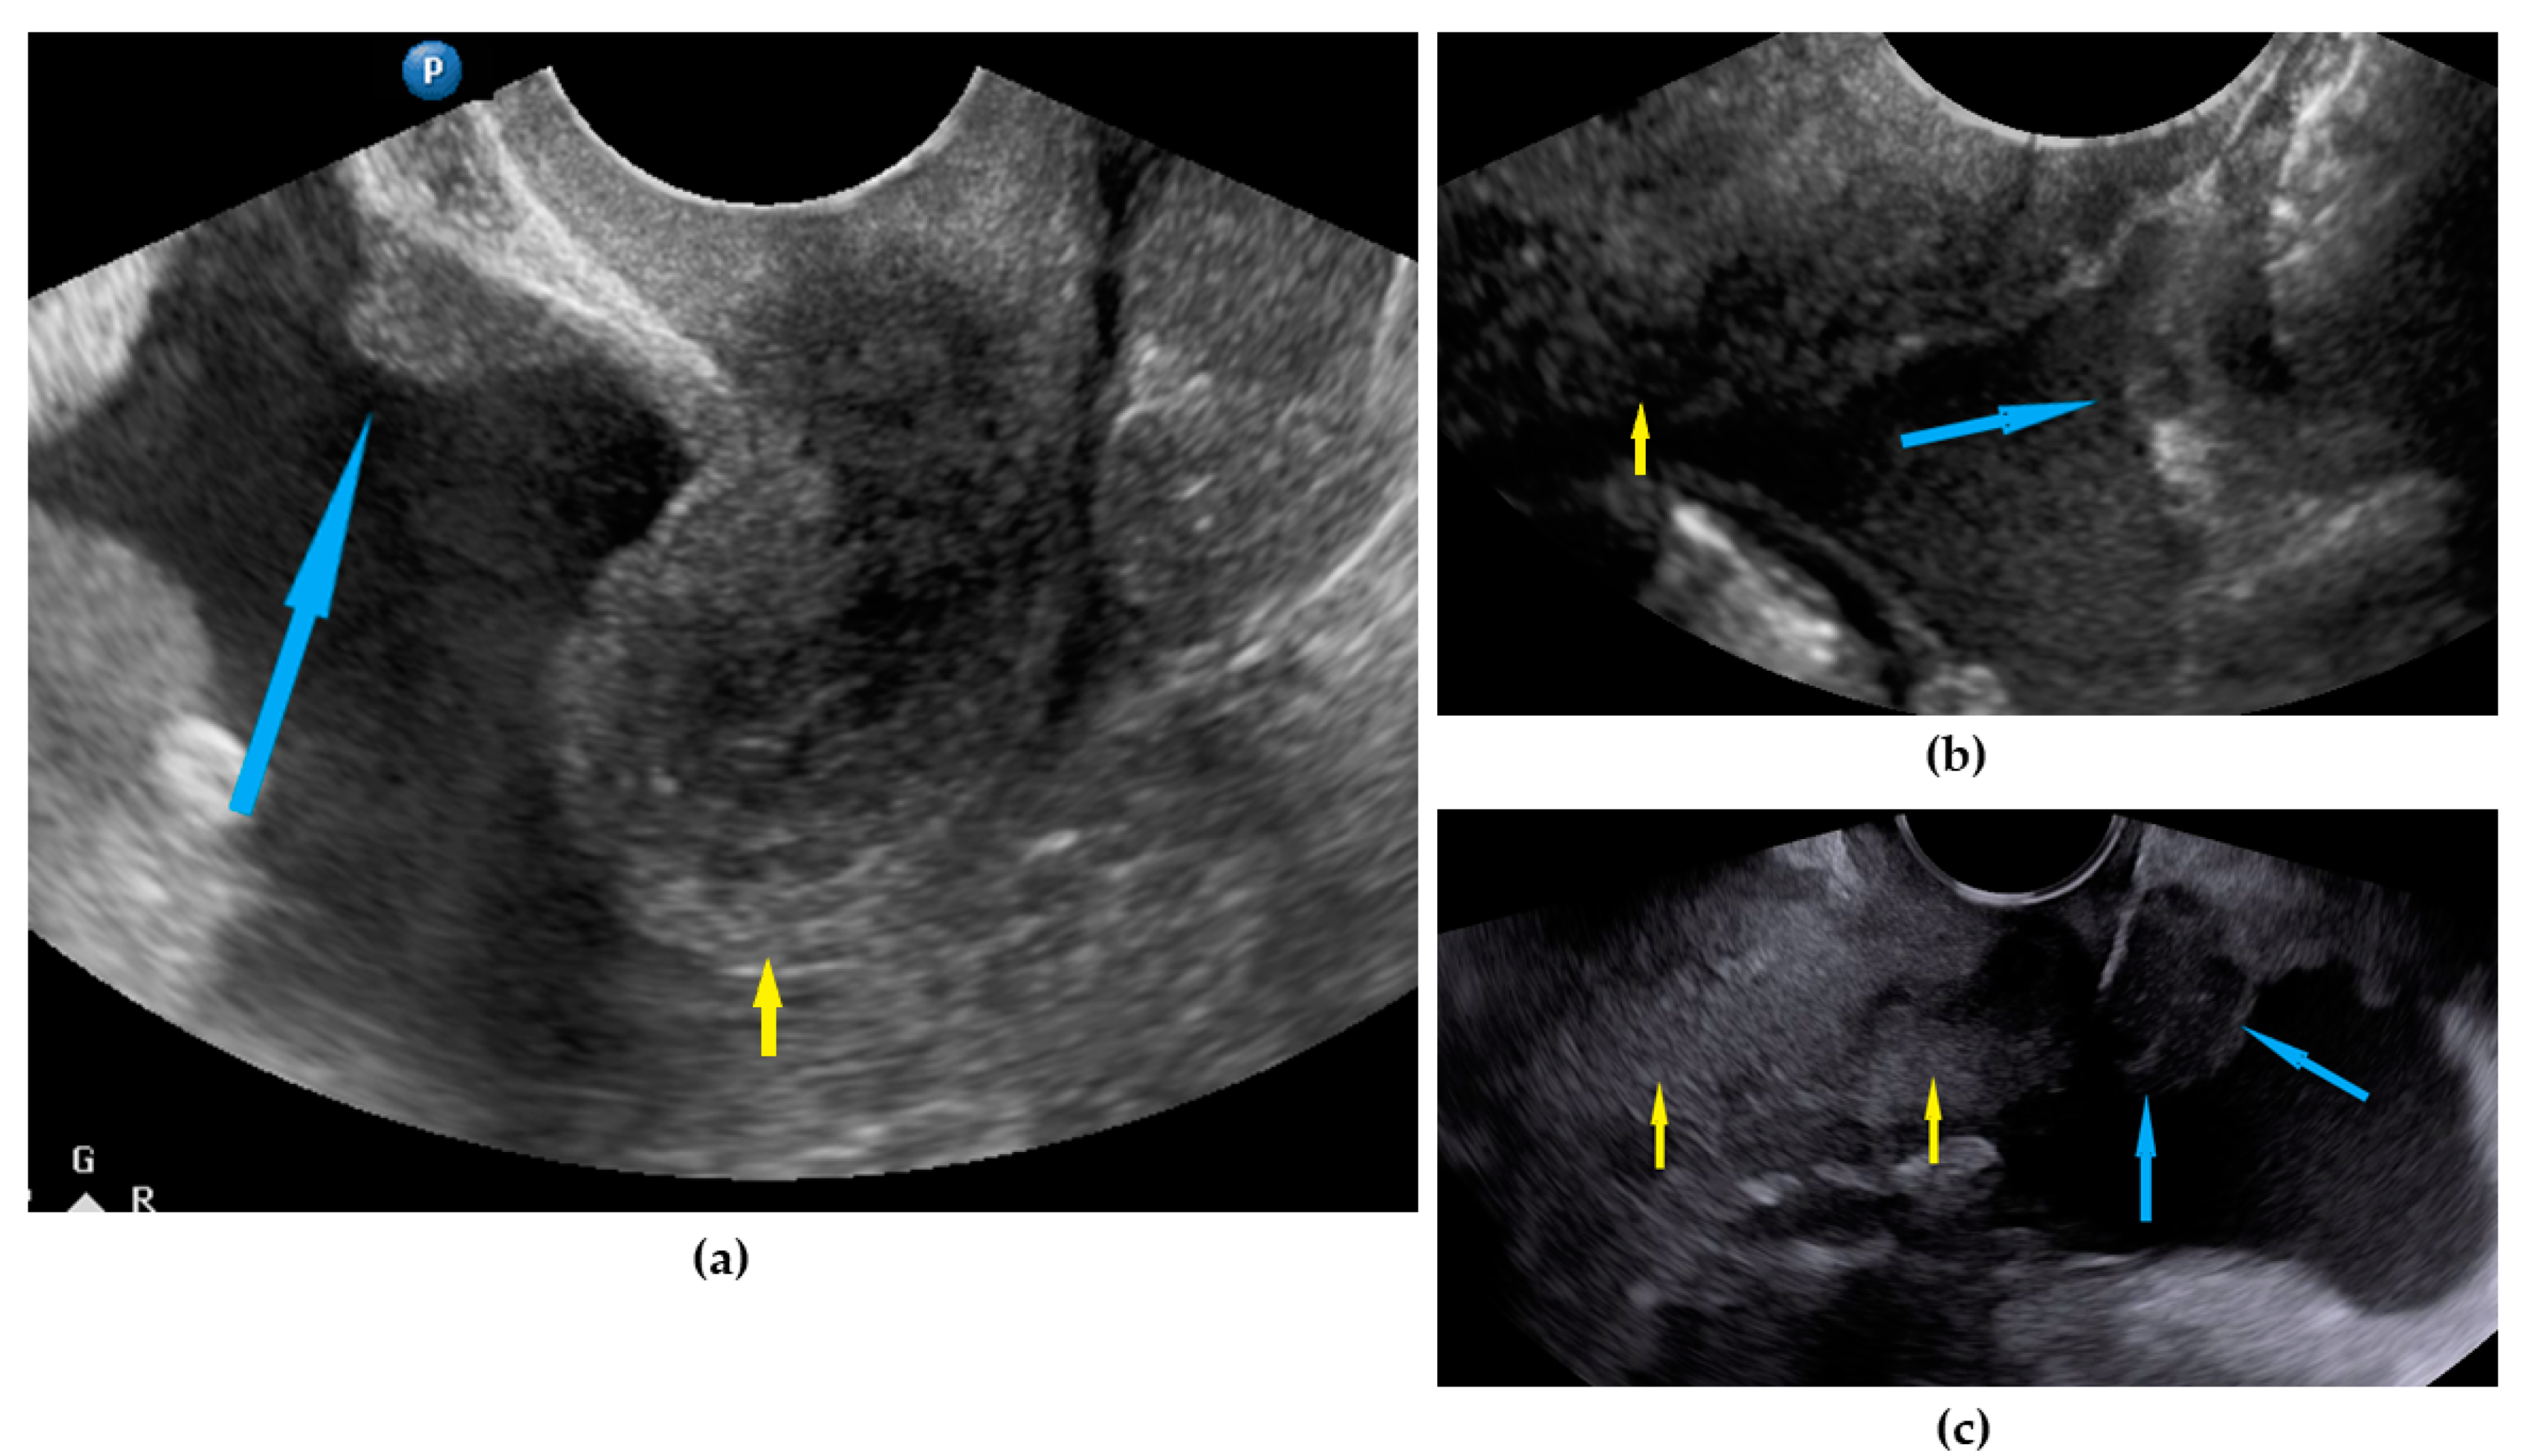

| Ascites | Fluid outside the pouch of Douglas, recorded as being present or absent 1 | Figure 5 | Video S5 |

| Liver, parenchymal lesions | Single or multiple focal parenchymal lesions (with a “halo“ sign, necrosis, and indistinct borders) in the liver. | Figure 6 | Video S6 |

| Liver hilum | Presence of nodules or rigid structures in the region of the hepatic hilum. | Figure 7 | Video S7 |

| Spleen, parenchymal lesions | Single or multiple focal parenchymal lesions (with a “halo“ sign, necrosis, and indistinct borders) in the spleen. | Figure 8 | Video S8 |

| Spleen, hilum | Presence of nodules or rigid structures in the region of the spleen hilum. | Figure 9 | Video S9 |

| Diaphragm, right | Carcinomatosis manifests as hypoechogenic lesions over the peritoneal surface of the right diaphragm. | Figure 10 | Video S10 |

| Diaphragm, left | Carcinomatosis manifests as hypoechogenic lesions over the peritoneal surface of the left diaphragm. | Figure 11 | Video S11 |

| Frozen pelvis | Massive pelvic involvement: hypoechogenic tissue in the peritoneum in the pouch of Douglas, forming cohesion between ovarian masses, bowel, uterus, and posterior pelvic wall. It manifests in the dynamic ultrasound examination: absence of sliding sign between the rectum and uterus/ovaries and between the uterus, urinary bladder, and pelvic walls. | Figure 12 | Video S12 |